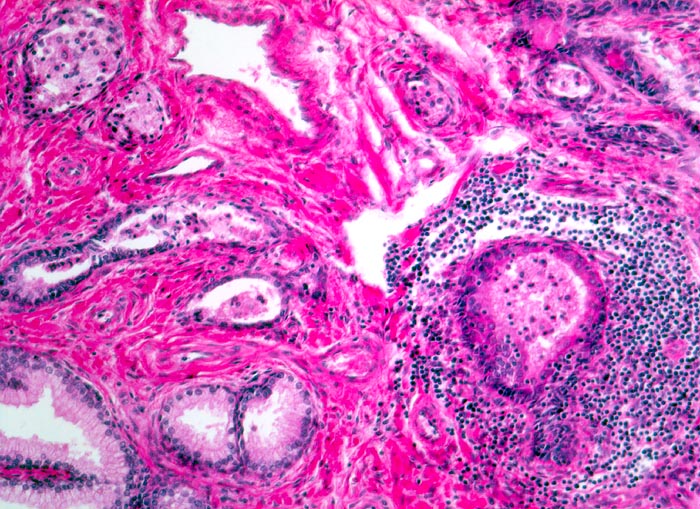

Basel 1MA/ Myoglanduläre Prostatahyperplasie

Myoglanduläre Prostatahyperplasie

Im Gegensatz zum Prostatakarzinom, welches in der Aussendrüse lokalisiert ist, finden sich die hyperplastischen Knoten vor allem in der Innendrüse. Makroskopisch ist die Prostata meist vergrössert und weist zentral weisse Knoten auf. Die myoglanduläre Prostatahyperplasie ist pathomorphologisch charakterisiert durch eine Proliferation von stromaler und epithelialer Komponente der Prostata im periurethralen Bereich. Die histologische Untersuchung von transurethral reseziertem Gewebe dient dem Ausschluss eines klinisch okkulten Karzinoms.

• Knotiges Parenchym.

• Organoid angeordnete, teils dilatierte grosse Drüsen eingebettet in ebenfalls vermehrtes fibroleiomyomatöses Stroma.

• Drüsen ausgekleidet von hochprismatischen sekretorischen Zellen (innen) mit unscheinbaren Nukleolen und durchgehender flacher Basalzellschicht (aussen).

• Konzentrisch geschichtetes hypereosinophiles Sekret in einigen Drüsenlumina (Corpora amylacea).

• Herdförmig geringes chronisches Entzündungsinfiltrat.